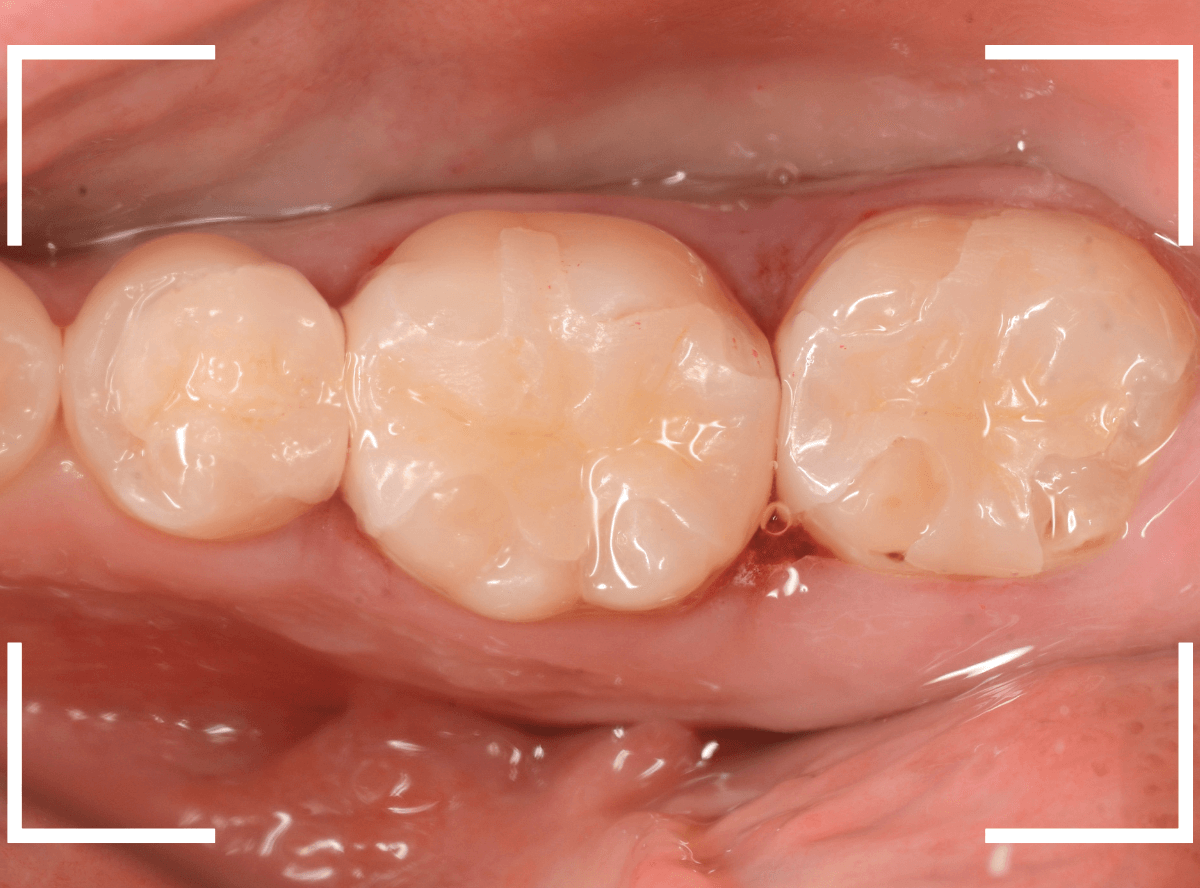

最終setした状態です。

左側の大臼歯2本が、ジルコニア・インレー

右側の小臼歯2本が、E-MAX・インレー

になります。

見た目にほとんど遜色ない仕上がりにできました。